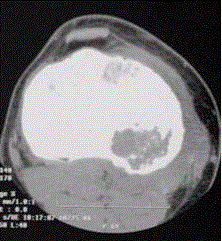

问题 患者男,15岁。右膝X线平片和CT检查见下图。 根据此病灶内部多发钙化,对其定性诊断的提示是

选项 A.良性 B.骨源性 C.软骨源性 D.纤维源性 E.恶性

答案 C